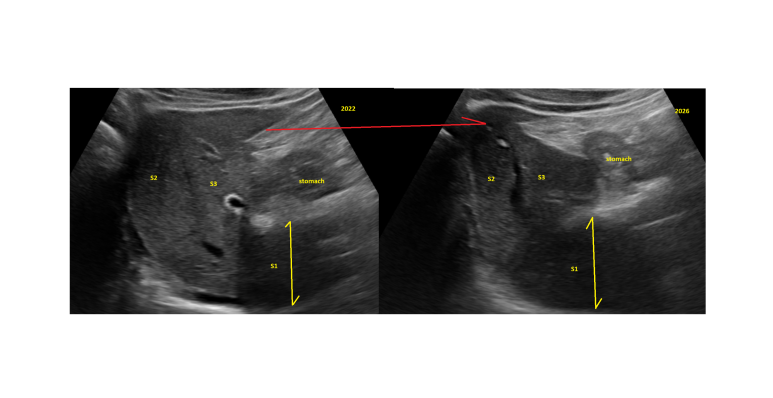

옆구리 통증에서 고환 통증으로... 요로결석의.. : 네이버블로그 https://blog.naver.com/ejercicio/223756689757 4년간 천식얘기는 하지 않다가.. 한번 슬쩍 .. : 네이버블로그 상기 요로결석, 충수돌기염, 천식 환자 이후엔 배가 조금만 불편해서 과거와 연관짓는 모습으로 보이며... 혈변도 가끔 있다고 하여 대장내시경 포함 검사함 담낭 주변 왼쪽엽과 S4번은 평탄화 혹은 결절성 변화가 있으며, 따라서 담낭은 앞쪽으로 노출되어 있다. (expanded GB fossa sign) 수직으로 보면 노란방향으로 위치해야할 담낭이 단의 단면에 붙어서 위쪽으로 향한 모습이다. 주변 간 영역의 부피가 감소했음을 시사 최초 초음파 (4년전) 에 같은 각도로 찍은 사진은 없어서 위의 사진과 비교는 못하지만, 늑간뷰에서 찍은 것을 보면 변화를 이해할 수 있다. 좌엽의 vertical view에서도 S2/S3 모두 상대적으로 작아